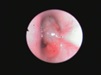

Причиной нарушения носового дыхания могут быть врожденные аномалии у котят и щенков. Например, кисты и полипы носовых ходов. Очень часто в нашей практике мы сталкиваемся с маленькими пациентами, в возрасте до года, с нарушением дыхания и различного рода выделениями из носовых ходов. Следует помнить, что в первую очередь, особенно у не вакцинированных животных следует исключить вирусные инфекции у котят и щенков, способные вызывать риниты. Кисты и полипы у молодых животных отлично диагностируются и легко удаляются с помощью эндоскопических технологий. Важна своевременная диагностика и удаление кист и полипов, так как со временем они могут привести к деформации костей лицевого черепа и тяжелым хронических гнойным ринитам.

Риноскопия - это эндоскопическое исследование носовых ходов и носоглотки с помощью эндоскопа. Для исследования носовых ходов чаще всего используются жесткие эндоскопы, которые вводятся через ноздри в носовые ходы. Для осмотра носоглотки удобнее применять гибкие эндоскопы, осмотр проводится через ротовую полость. Сама процедура риноскопии проводится с активной санацией физиологическим раствором, что так же оказывает лечебный эффект, особенно при хронических и гнойных ринитах. Во время исследования осматриваются все носовые ходы ( вентральный, средний, дорсальный), а так же полость носоглотки, оценивается цвет слизистой, характер ее повреждений, оценивается проходимость и наличие инородных предметов, кист и новообразований. При обнаружении подозрительных участков слизистой, при хронических ринитах, новообразованиях- проводится взятие материла для гистологического исследования. Гистологическое исследование позволяет поставить более точный диагноз и исключить онкологическую природу заболевания.

Во время риноскопии помимо осмотра проводится и удаление полипов, кист и новообразований. Удаление образований выполняется с помощью специальных эндоскопических инструментов, очень важно, что удаление проводится под эндоскопическим контролем.

Кисты носовых ходов